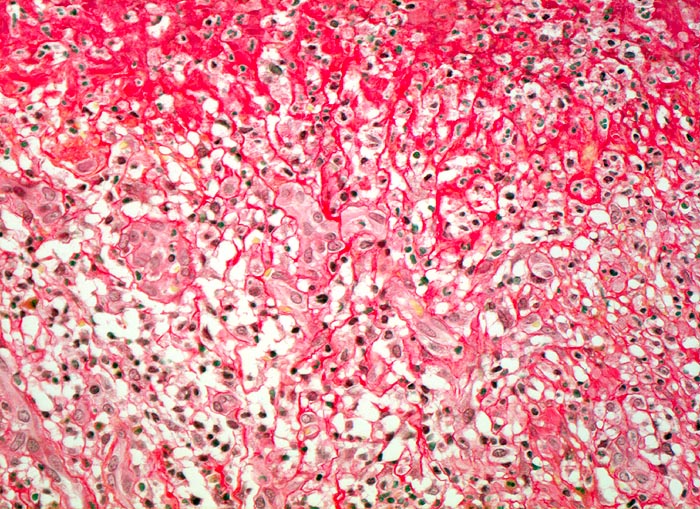

Das akute Ulkus ist rund, oval oder seltener polyzyklisch begrenzt und liegt meist im Schleimhautniveau. Das chronische Ulkus ist häufig kreisrund und im Längsschnitt trichter- oder treppenförmig. Die Schleimhautränder können lippenförmig über den Ulkusgrund hinausragen. Palpatorisch ist das chronische Ulkus aufgrund der narbigen Fibrose induriert. Die Schleimhautfalten laufen sternförmig auf das Ulkuszentrum zu. Das chronische Ulkus tritt zu 10%, das akute zu 25% multipel auf. Mikroskopisch zeigt das chronische Ulkus eine typische Schichtung (s. Bilder). Die Gefässe im Ulkusgrund zeigen eine starke Intimaproliferation mit teilweiser oder vollständiger Obliteration der Gefässlichtung. Morphologische Veränderungen in der übrigen Magenschleimhaut geben einen Hinweis auf die Ätiologie des Ulkus (Typ B oder C Gastritis).